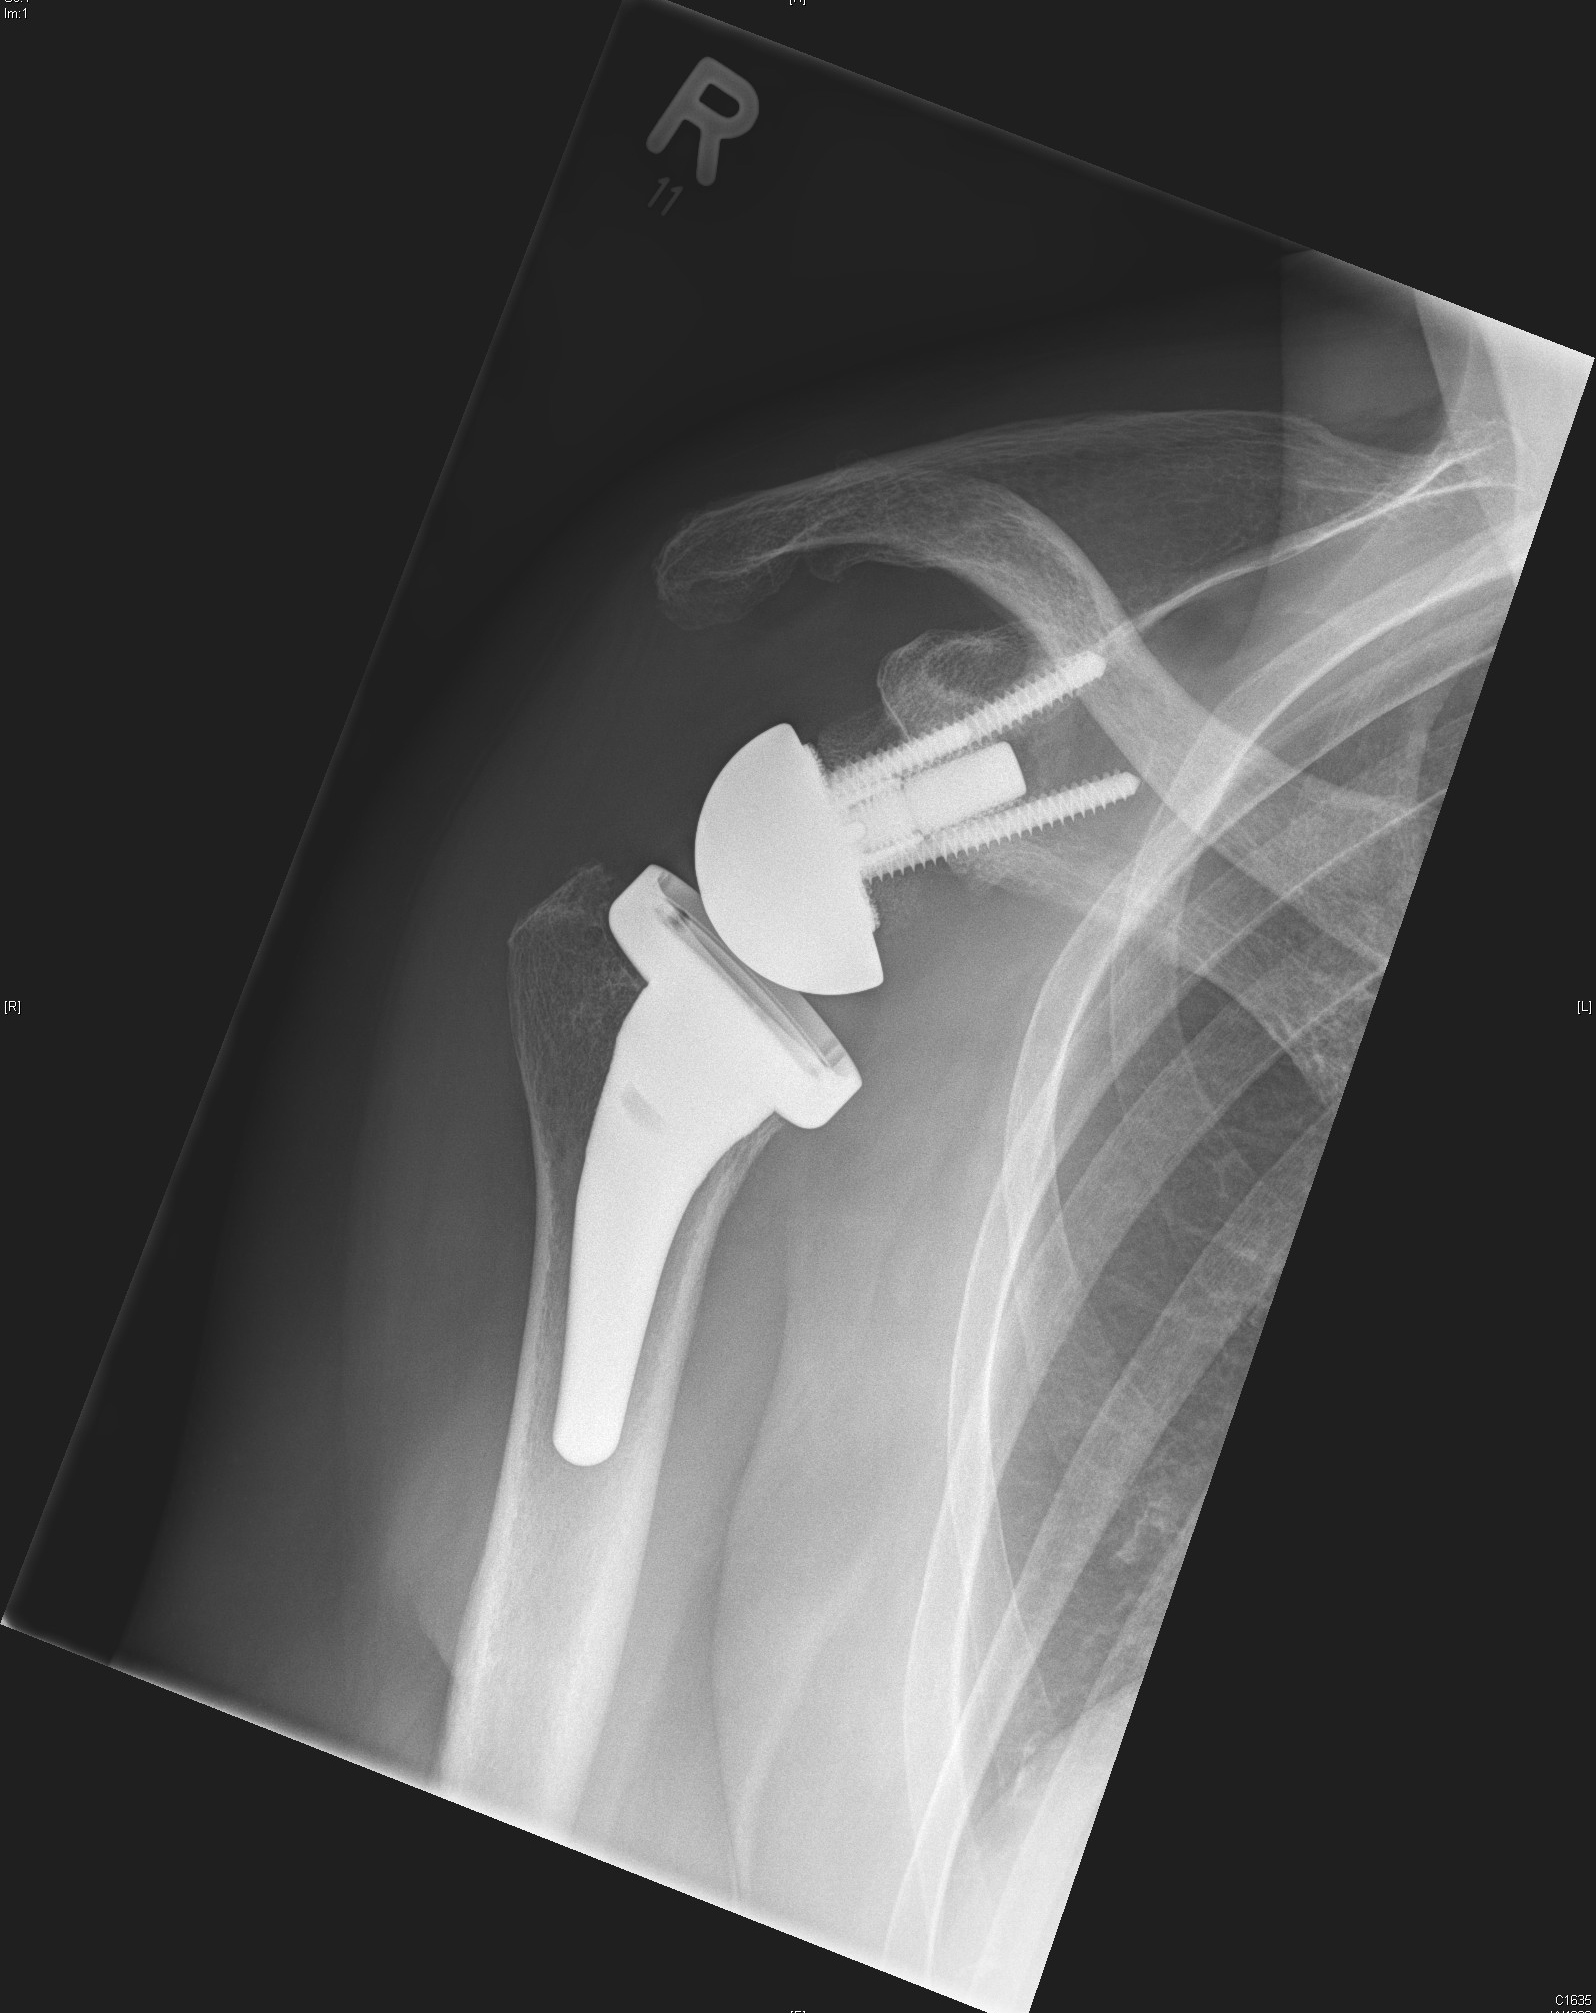

Umgekehrte (Inverse) Schulterprothese